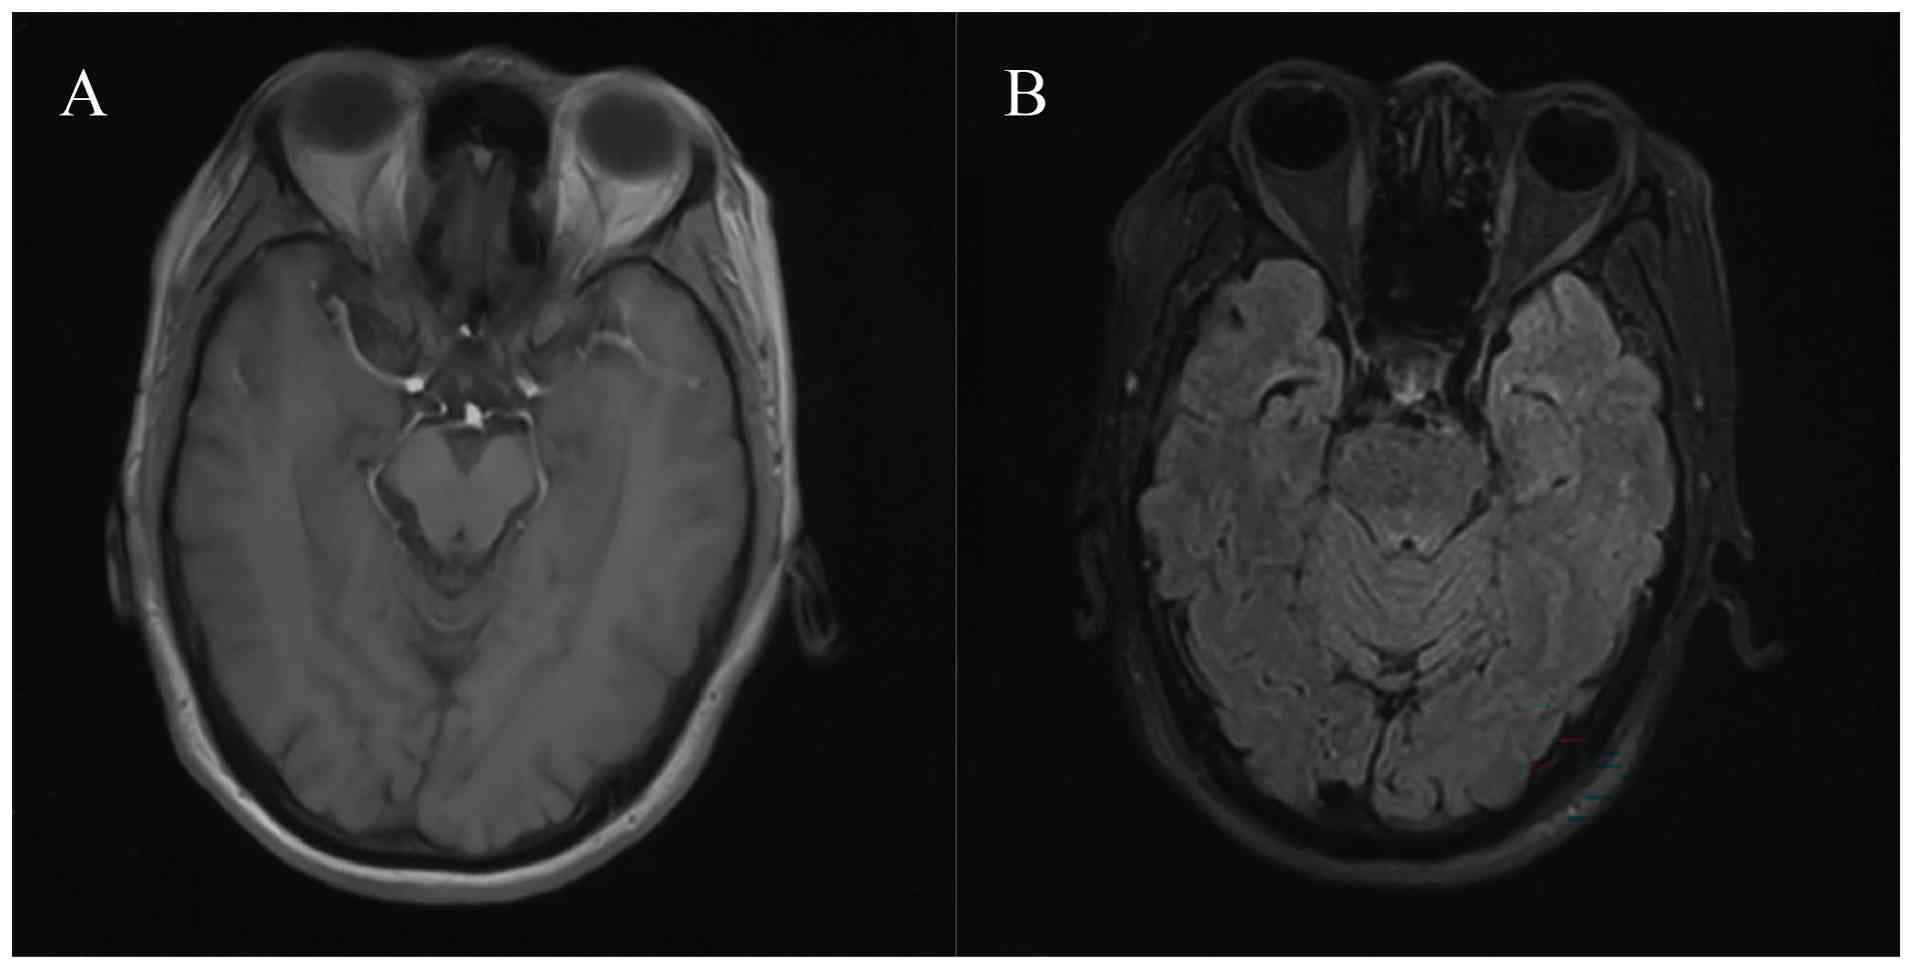

Subsequently, she presented to Peking Union Medical College Hospital and underwent evaluations. The results of cerebrospinal fluid (CSF) analysis 3 days after the development of these neurological problems included lymphocytic pleocytosis [white blood cells, 16/µl (normal range, 0–8/µl); 90% lymphocytes (normal range, 40–80%); 5% monocytes (normal range, 14–45%); and 5% neutrophils (normal range, 0–6%)]; an elevated protein level [95 mg/dl (normal range, 15–45 mg/dl)]; a normal glucose level and IgG index; and no oligoclonal bands or tumor cells were observed. Polymerase chain reaction testing of CSF did not detect herpes simplex virus, varicella-zoster virus, cytomegalovirus or human herpesvirus-6 DNA. Anti-Hu antibodies were detected in the serum and CSF using immunoblotting (Hu/Yo/Ri/Ma2/Ta/CV2/amphiphysin antibodies; cat. no. DL 1111-1601-2G; EUROIMMUN; used in accordance with the kit manufacturer's instructions). Neuronal cell surface antibodies were all negative. Brain MRI depicted swelling of the bilateral medial temporal lobes, with patchy prolonged T2 signal and high fluid-attenuated inversion recovery (FLAIR) signals in both hippocampi (Fig. 4).

Swelling of the bilateral medial

temporal lobes, with (A) patchy prolonged T2 signal and (B) high

fluid-attenuated inversion recovery signal in both hippocampi was

indicated by brain magnetic resonance imaging at the onset of

neurological symptoms. The arrows indicate the lesion.

Figure 4.

Swelling of the bilateral medial temporal lobes, with (A) patchy prolonged T2 signal and (B) high fluid-attenuated inversion recovery signal in both hippocampi was indicated by brain magnetic resonance imaging at the onset of neurological symptoms. The arrows indicate the lesion.